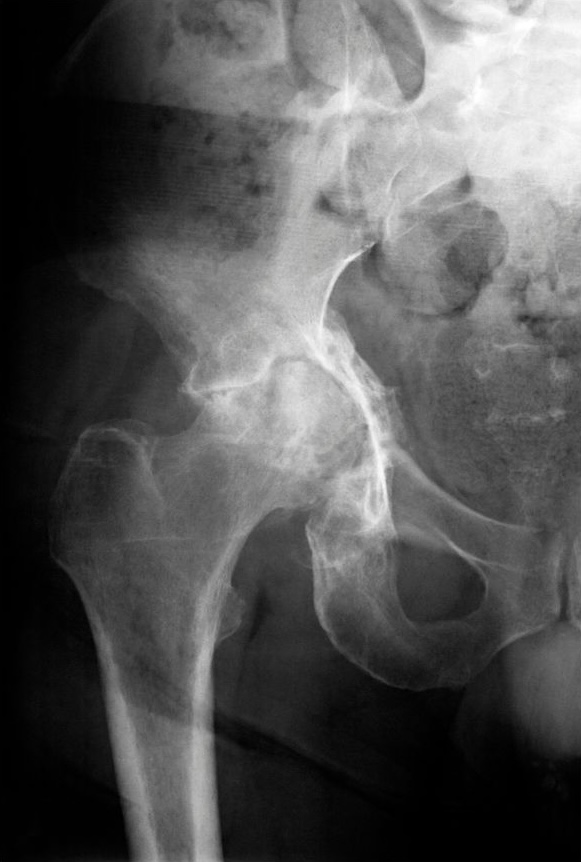

ただ、関節の変形の程度が大きく、筋肉に大きな負担がかかっている場合には、どうしても時間が必要になってくるケースが多くなってしまいます。